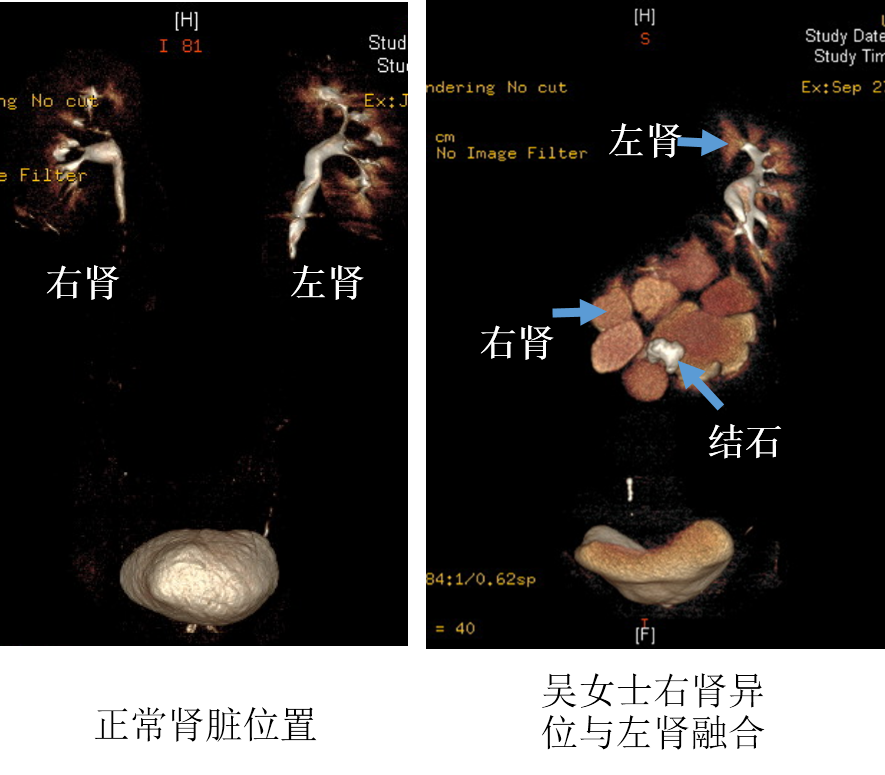

北京清华长庚医院10月18日电 (通讯员 宋海峰)今年51岁的吴女士,3个月前突然感觉自己左侧腰腹部疼痛不适,在当地医院就诊后才知道是患上了肾结石,但棘手的是,她还同时被发现是融合肾,本应位于右侧的肾脏大部分长在了身体的左侧,与左侧肾脏下端融合在一起,完全偏离正常位置,解剖结构极为罕见,而肾结石就以散在、多发的形态位于异位的肾脏内。

正常形态的肾脏位于后腰部,在腹腔后方、脊柱的两侧后方。对于肾结石手术,传统的经皮肾镜需要经过后腰部穿刺,建立手术通道进行碎石。但吴女士患有结石的异位肾却位于脊柱及腹腔大血管的前方,从后方穿刺不仅很难建立通道,而且无法触及结石。腰部手术“行不通”后,在当地医院的推荐下,吴女士慕名来到清华大学附属北京清华长庚医院泌尿外科。